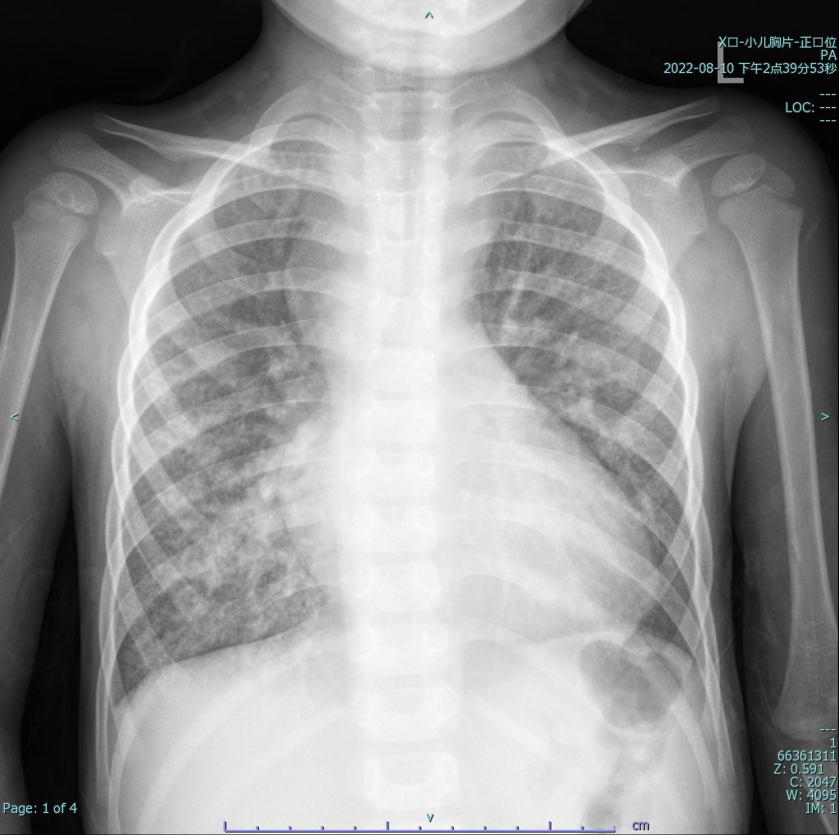

Laboratory testing showed hemoglobin 225 g/L and hematocrit 73.3%. Arterial blood gas revealed PO©ü 30.7 mmHg and SO©ü 58.1%. Chest X-ray showed cardiomegaly (cardiothoracic ratio 0.6) and increased pulmonary markings. Echocardiography demonstrated a patent Glenn anastomosis. Contrast-enhanced CT revealed absence of the main pulmonary artery and diffuse pulmonary arteriovenous malformations (PAVMs) in both lungs, most prominent in the lower lobes.